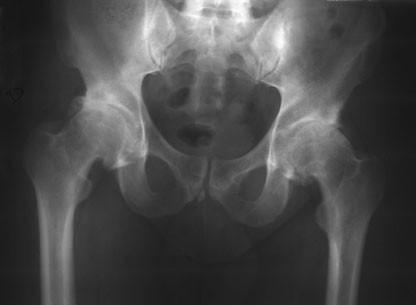

Secuencias Radiológicas

SE APRECIA UNA LINEA DE COLAPSO SUBCONDRAL EL SIGNO DE LA MEDIA LUNARADIOLOGIA NORMAL EL DIAG SE PUEDE REALIZAR POR RESONANCIA MAG

COLAPSO AFECTA LA SUPF SUBCONDRAL PERDIENDO SU MORFOLOGIA NORMAL

LA INCONGRUENCIA ARTICULAR PRODUCE PERDIDA DEL GROSOR DEL CARTILAGO Y CAMBIOS EN EL ACETABULO

RADIOLOGIA